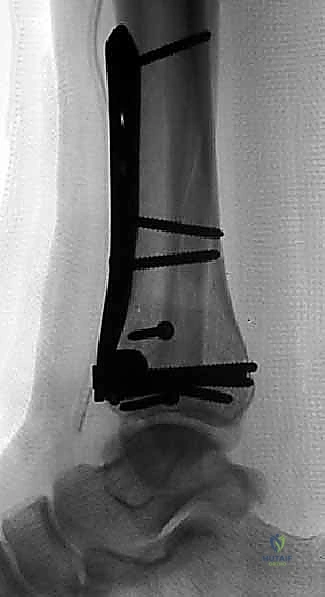

العلاج الجراحي: التثبيت الداخلي المفتوح (ORIF) - المعيار الذهبي

بالنسبة لجميع كسور البيلون المنزاحة والمفتتة، يعتبر التثبيت الداخلي المفتوح (Open Reduction and Internal Fixation - ORIF) هو العلاج القياسي والمعيار الذهبي.

في صنعاء، يطبق الأستاذ الدكتور محمد هطيف المبادئ الأربعة الكلاسيكية التي وضعها (Ruëdi and Allgöwer) والتي تم تحديثها بالتقنيات الحديثة، وتتمثل أهدافها في:

1. إعادة بناء مفصلية دقيقة (Anatomic Articular Reduction): لا مجال للخطأ هنا. يجب إعادة بناء السطح المفصلي بدقة المليمتر لتجنب احتكاك الغضاريف وحدوث خشونة مبكرة.

2. استعادة طول الطرف ومحاذاته (Restoration of Length and Alignment): لمنع العرج وتوزيع الوزن بشكل غير متساوٍ على الركبة والورك.

3. التطعيم العظمي (Bone Grafting): لملء الفراغات الناتجة عن انضغاط العظم الإسفنجي.

4. تثبيت الكسر المستقر (Stable Fixation): باستخدام شرائح ومسامير متطورة للسماح بالحركة المبكرة للمفصل.

قبل دخول غرفة العمليات لإجراء الجراحة النهائية، يقوم الدكتور هطيف برسم خطة تفصيلية. يتم استخدام الأشعة المقطعية لتحديد أماكن الشقوق. القاعدة الذهبية هي: يجب أن يكون هناك مسافة لا تقل عن 7 سنتيمترات بين أي شقين جراحيين (مثلاً شق للشظية وشق للظنبوب) لضمان عدم انقطاع التروية الدموية عن الجلد بينهما (Skin Bridge).

الخطوات الجراحية التفصيلية: إبداع التثبيت الداخلي المفتوح (ORIF)